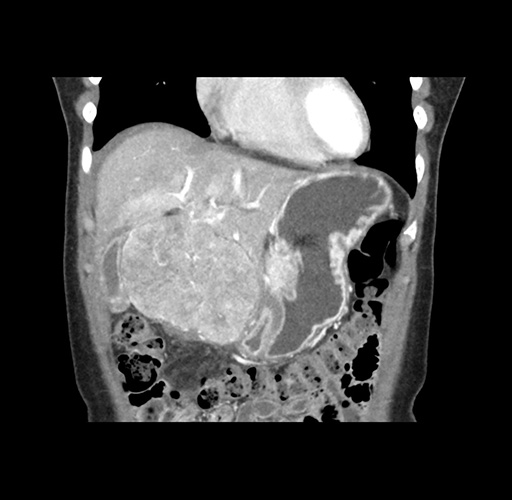

Imaging Analysis

Look through the patient's CT scan to identify any areas of concern for the necessary procedure.

Based on your CT findings, which issue(s) would give reason for "planned slowing down moment(s)" in this case?

Considering a standard left lateral sectionectomy procedure, what step(s) of the operation would you do differently in this case ?